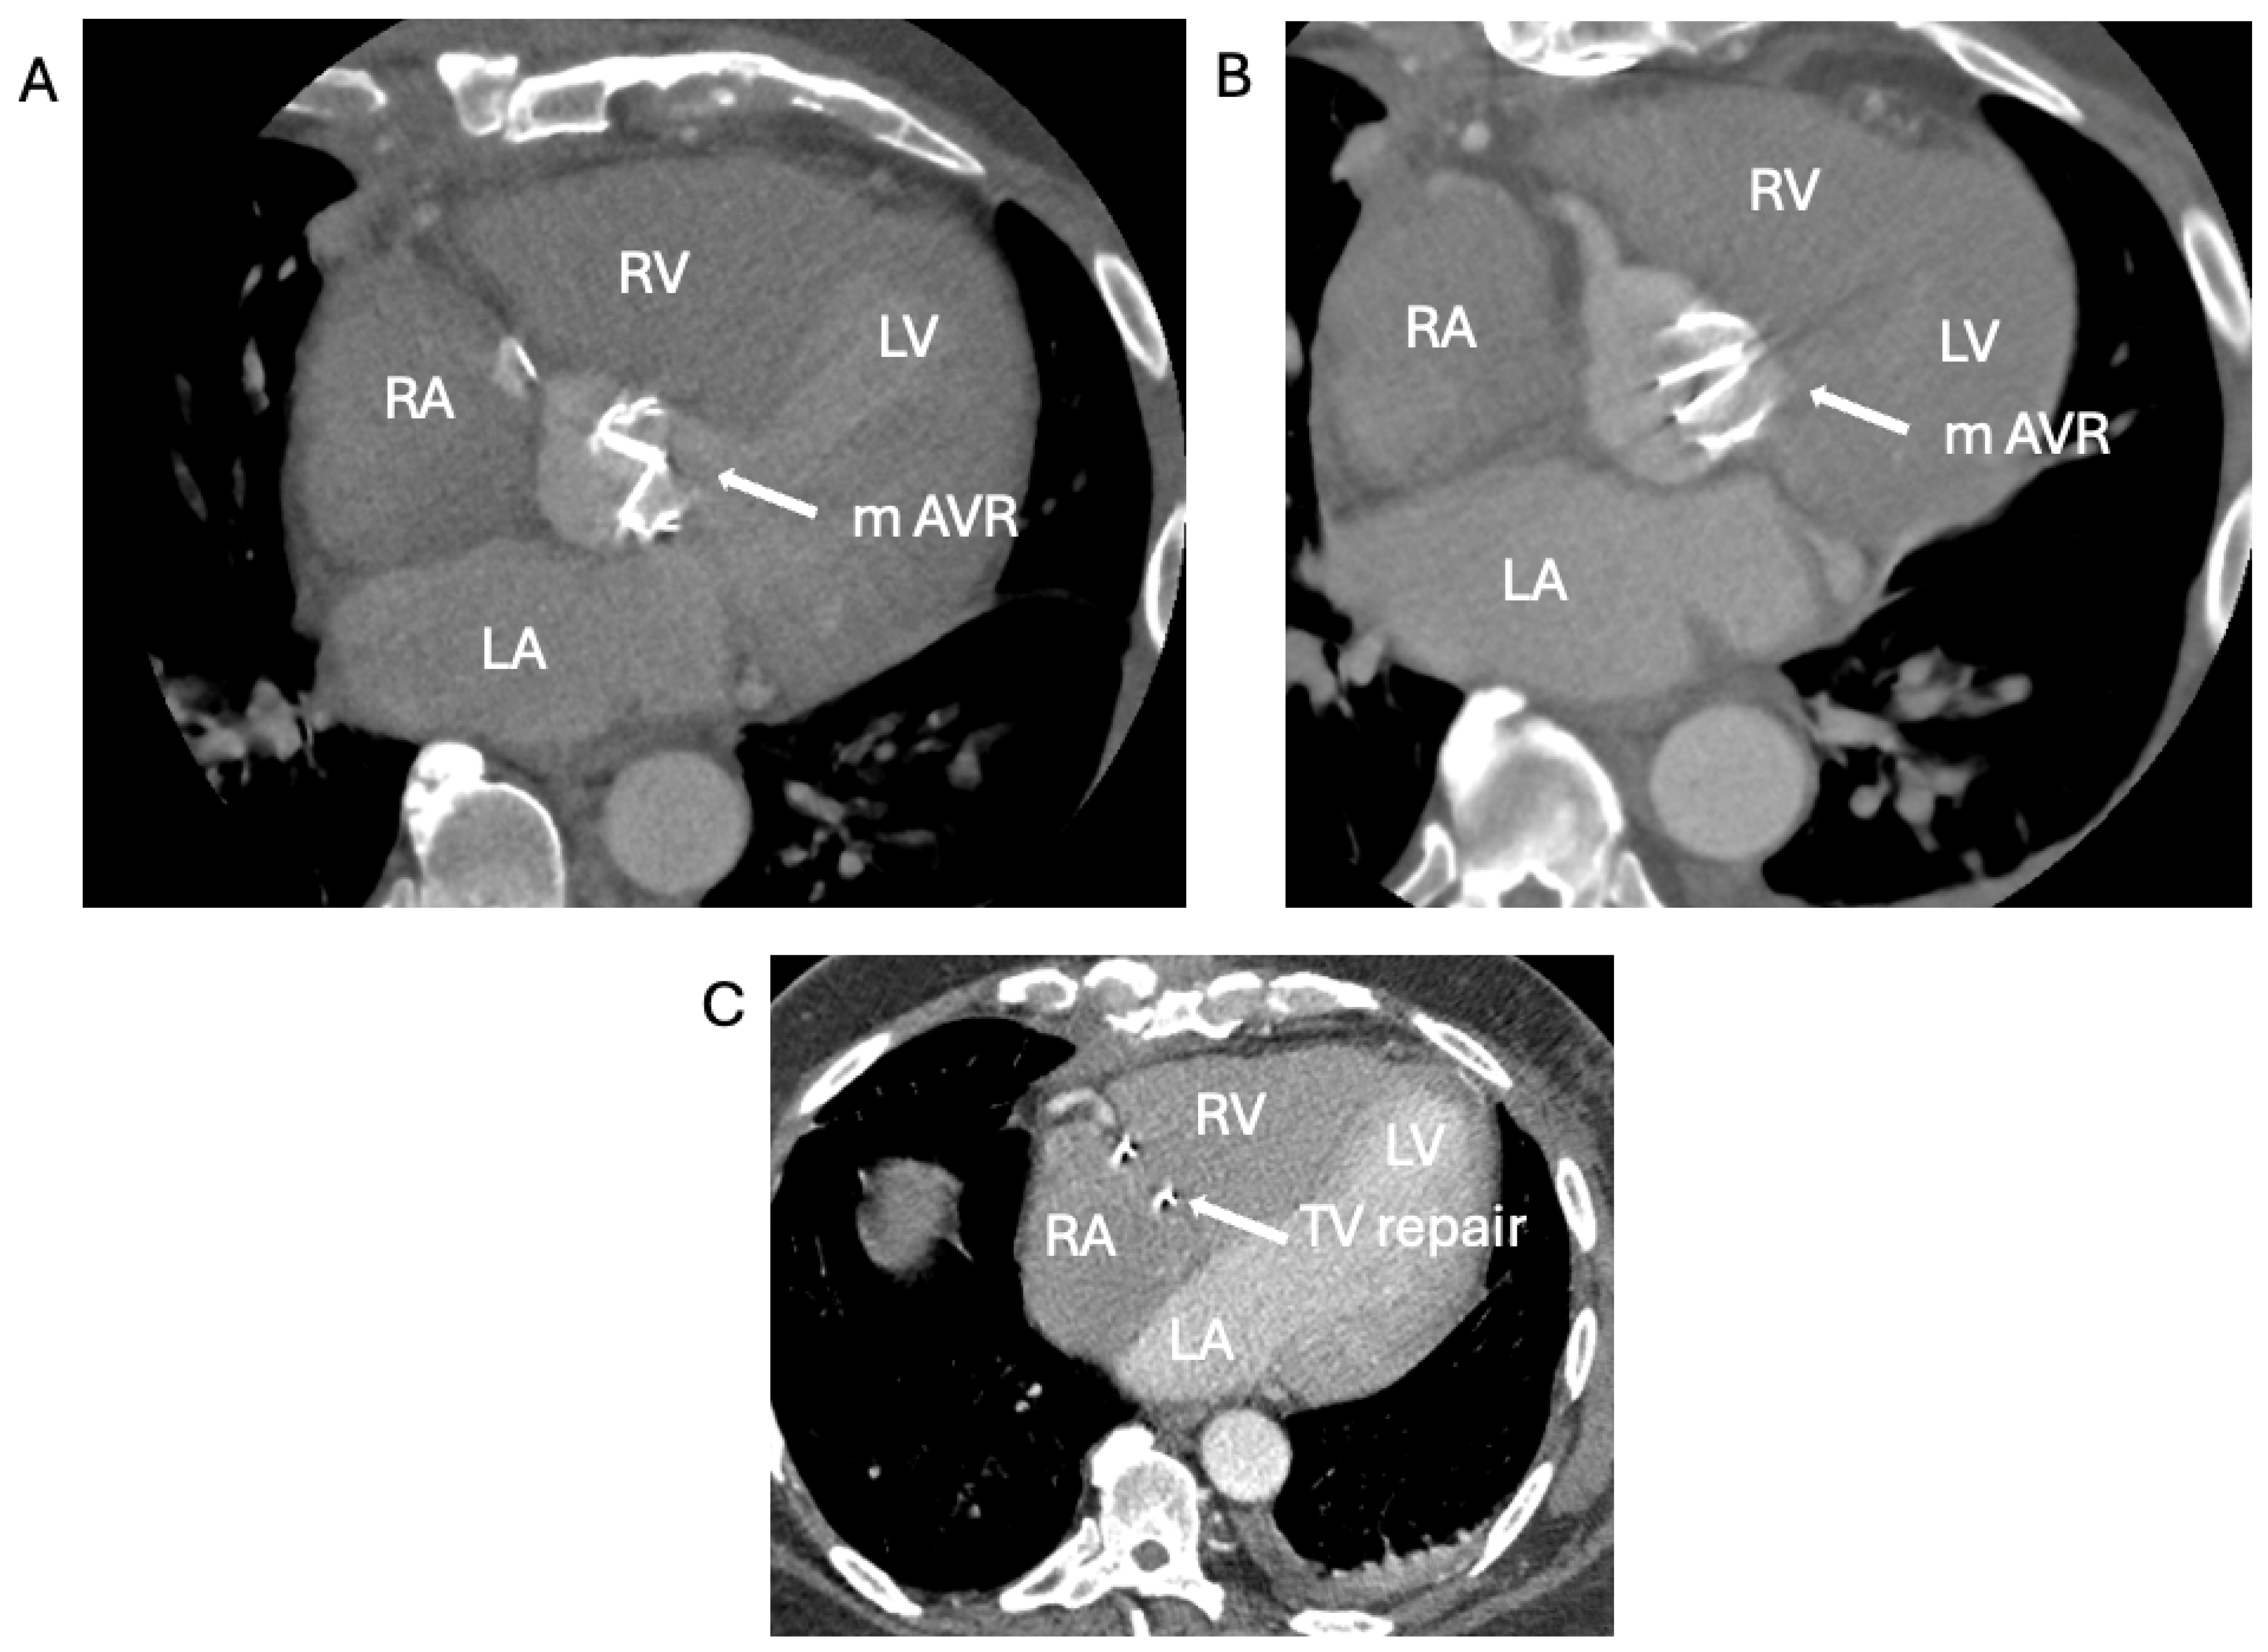

1.1.3. Case 3